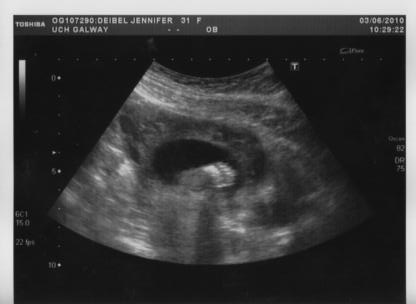

Most importantly, we found out that baby is perfectly healthy, right on track with grown, and all organs and limbs look perfect. When the scan started, baby was sitting in the breech position, with it's bottom down and head up pointing towards my lungs. In this position, it's often difficult to get a good gender shot, but our little one cooperated anyway.

Baby Deibel, with pointer finger on lips, pondering whether or not to let us see if it's a boy or girlThankfully, they decided to cooperate and showed us that they are a healthy....

BOY!!!!